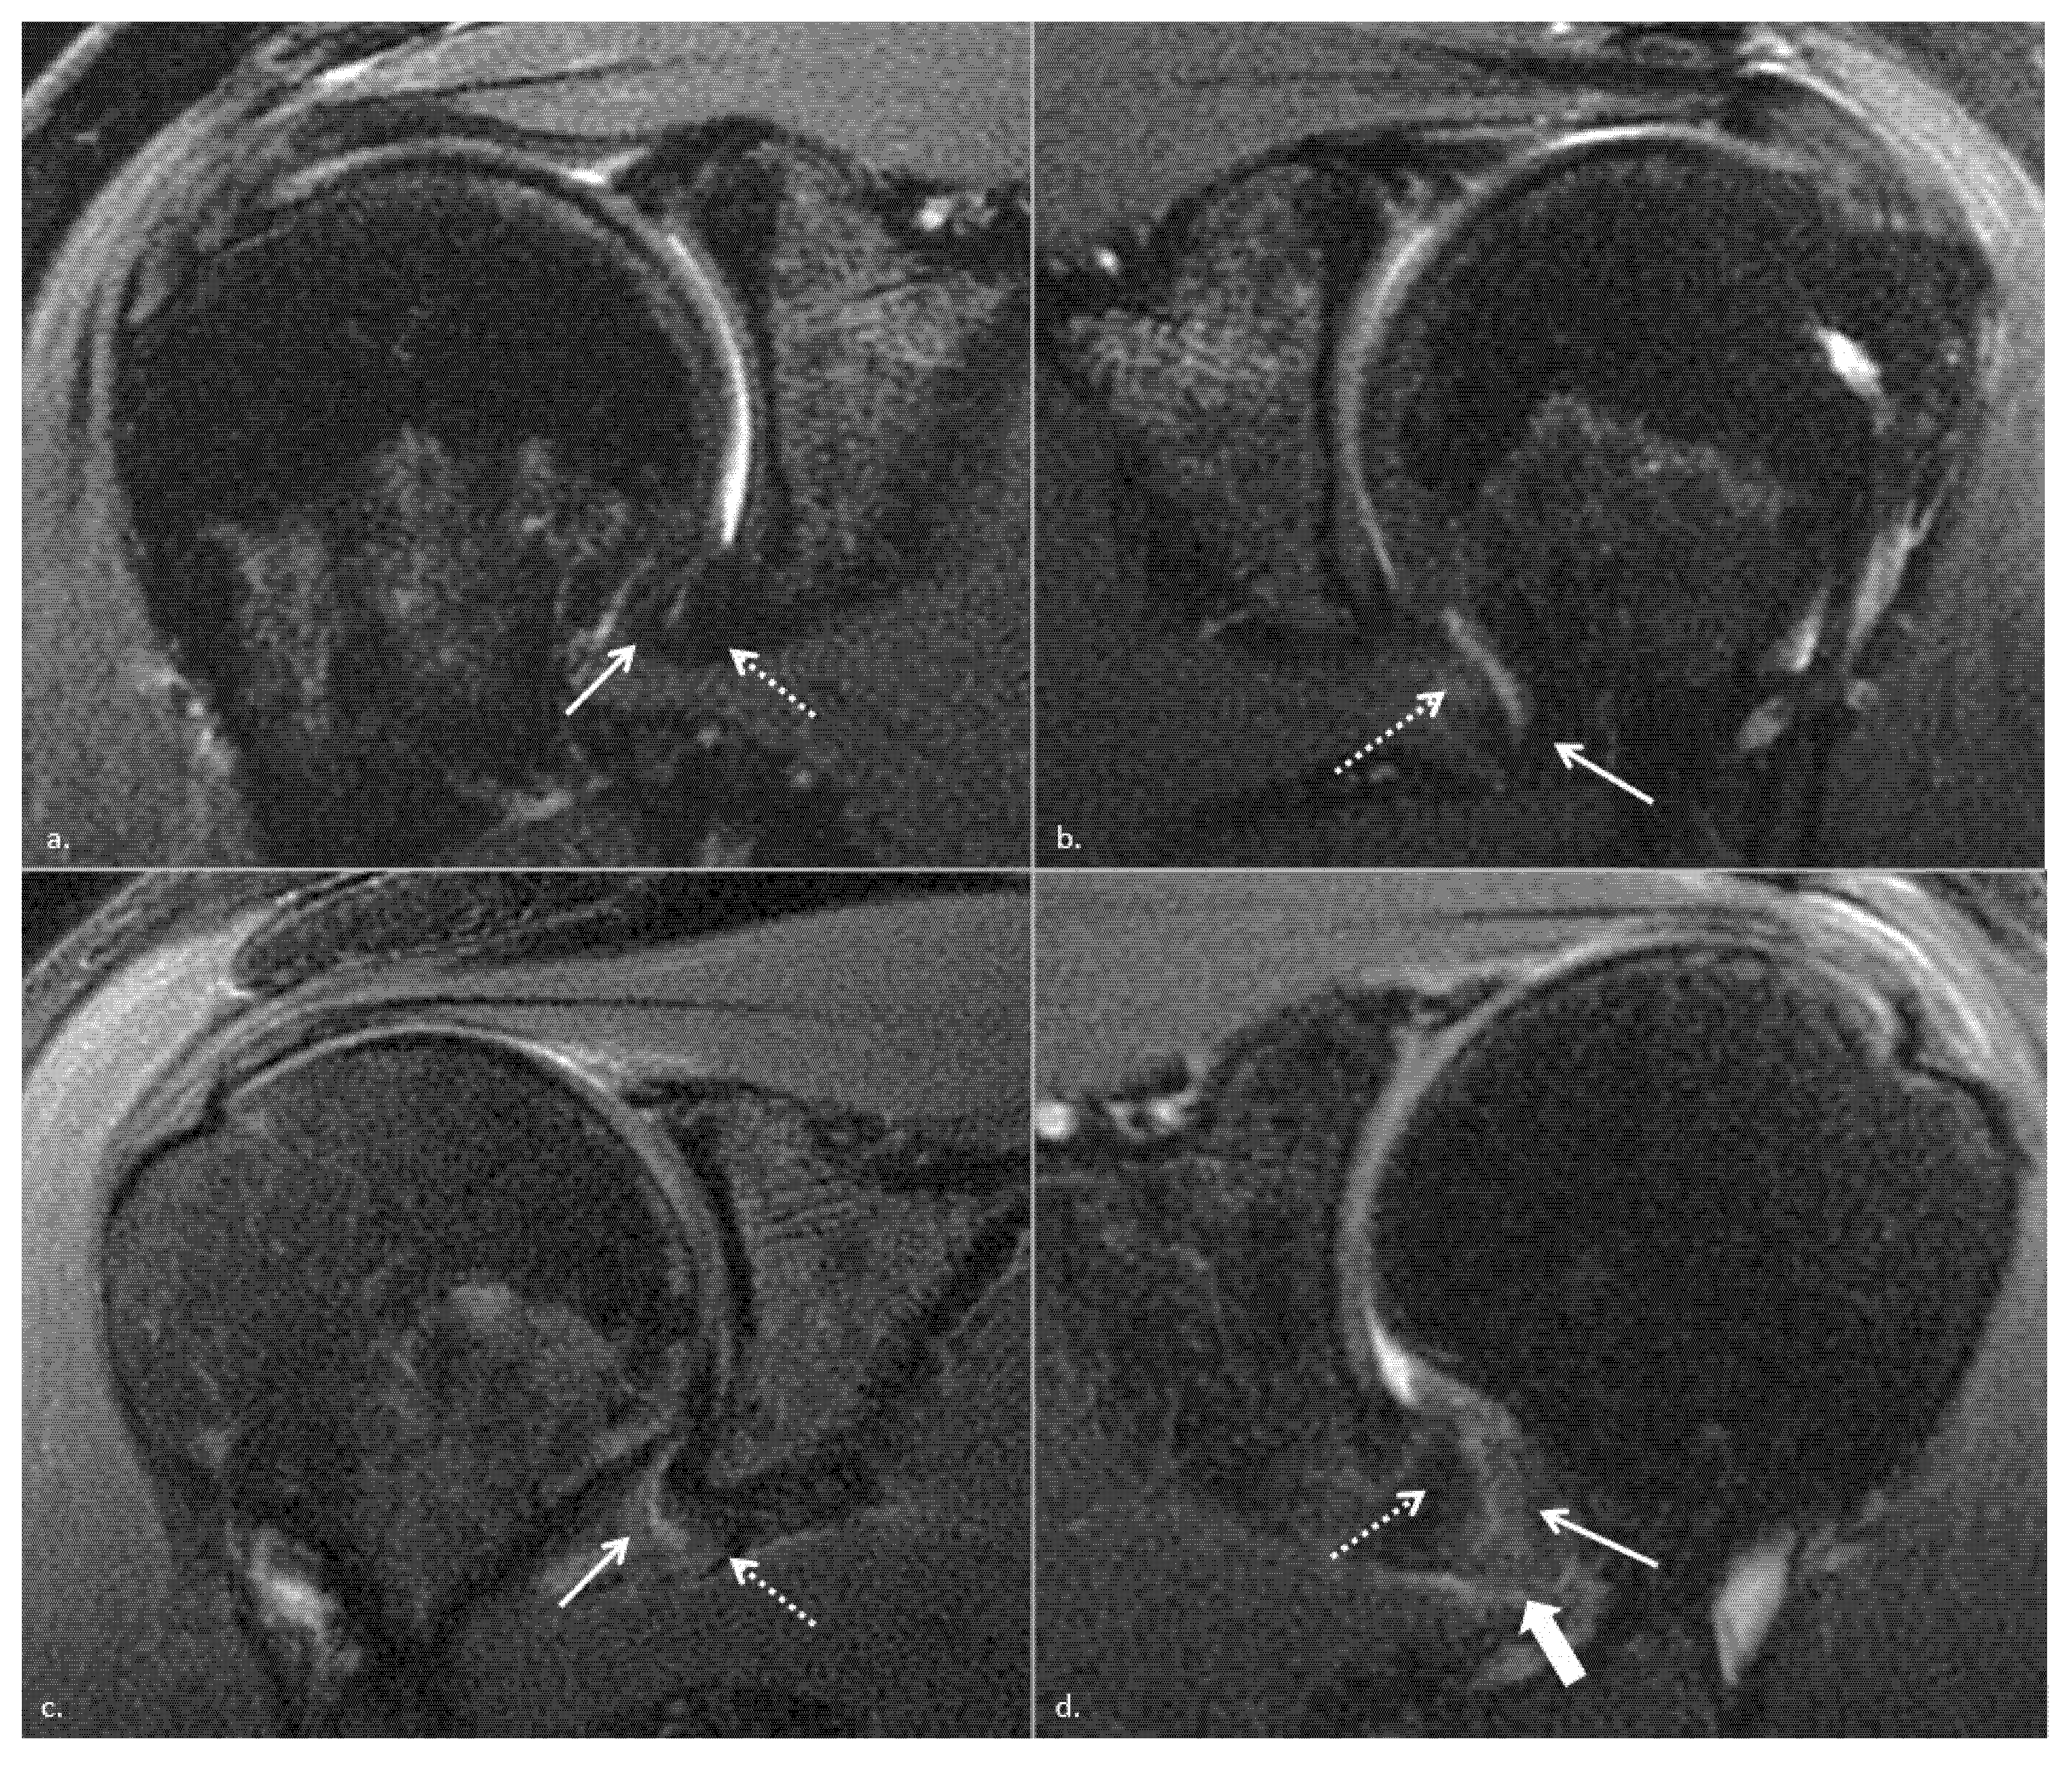

From www.mdpi.com

JCM Free FullText MR Imaging Biomarkers for Clinical Impairment Adhesive Capsulitis Empty Can Test It reduces the subacromial space thus eliciting pain if impingement is present. Understand the pathophysiology of rotator cuff tears and adhesive capsulitis. She states that she has difficulty sleeping at night on the right side and experiences significant. Differentiate signs and symptoms of rotator cuff tears and. Empty can test this is the same test that is used to check. Adhesive Capsulitis Empty Can Test.

From www.ajronline.org

Evaluation of Adhesive Capsulitis of the Shoulder With FatSuppressed Adhesive Capsulitis Empty Can Test She states that she has difficulty sleeping at night on the right side and experiences significant. Differentiate signs and symptoms of rotator cuff tears and. Understand the pathophysiology of rotator cuff tears and adhesive capsulitis. It reduces the subacromial space thus eliciting pain if impingement is present. Stiffness or loss of motion may be the major symptom in patients with. Adhesive Capsulitis Empty Can Test.

From www.sportsmedreview.com

MRI Findings in Adhesive Capsulitis of the Shoulder Sports Medicine Adhesive Capsulitis Empty Can Test Differentiate signs and symptoms of rotator cuff tears and. Understand the pathophysiology of rotator cuff tears and adhesive capsulitis. Adhesive capsulitis (also known as frozen shoulder) is a condition of the shoulder characterized by functional loss of both passive and active shoulder motion commonly. She states that she has difficulty sleeping at night on the right side and experiences significant.. Adhesive Capsulitis Empty Can Test.